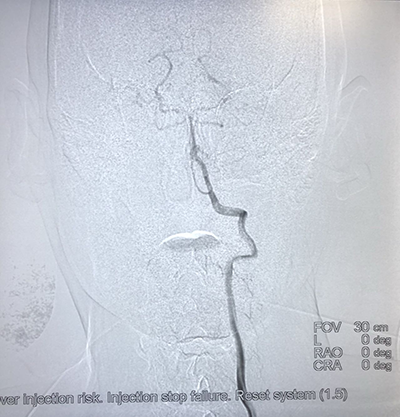

(腦腫瘤的介入治療)(子宮肌瘤的介入治療)